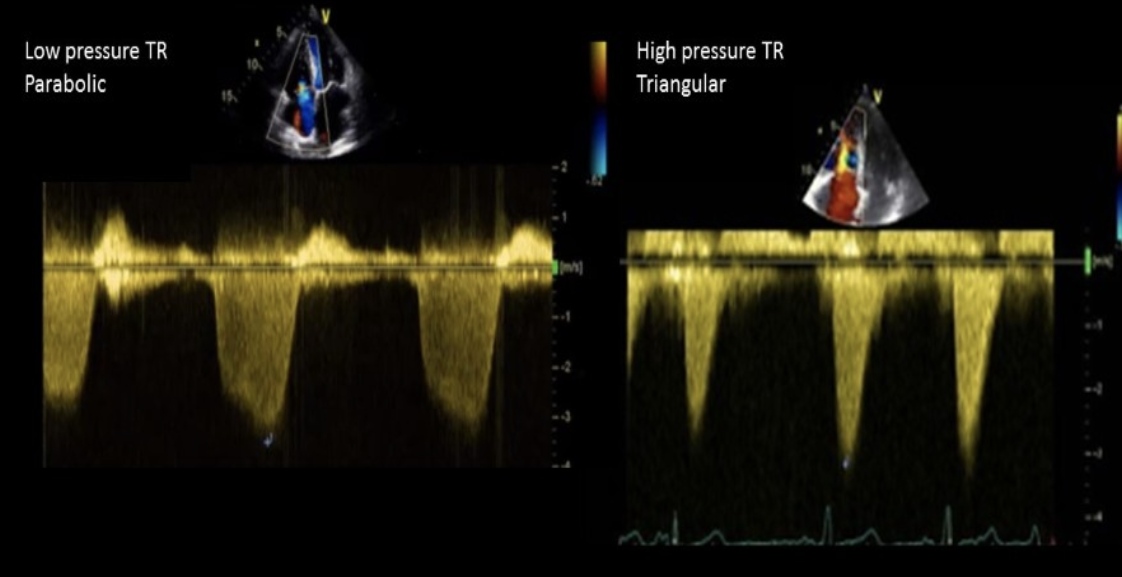

Doppler evaluation of mild TR demonstrates?

Parabolic waveform

Doppler evaluation of severe TR demonstrates?

Triangular waveform